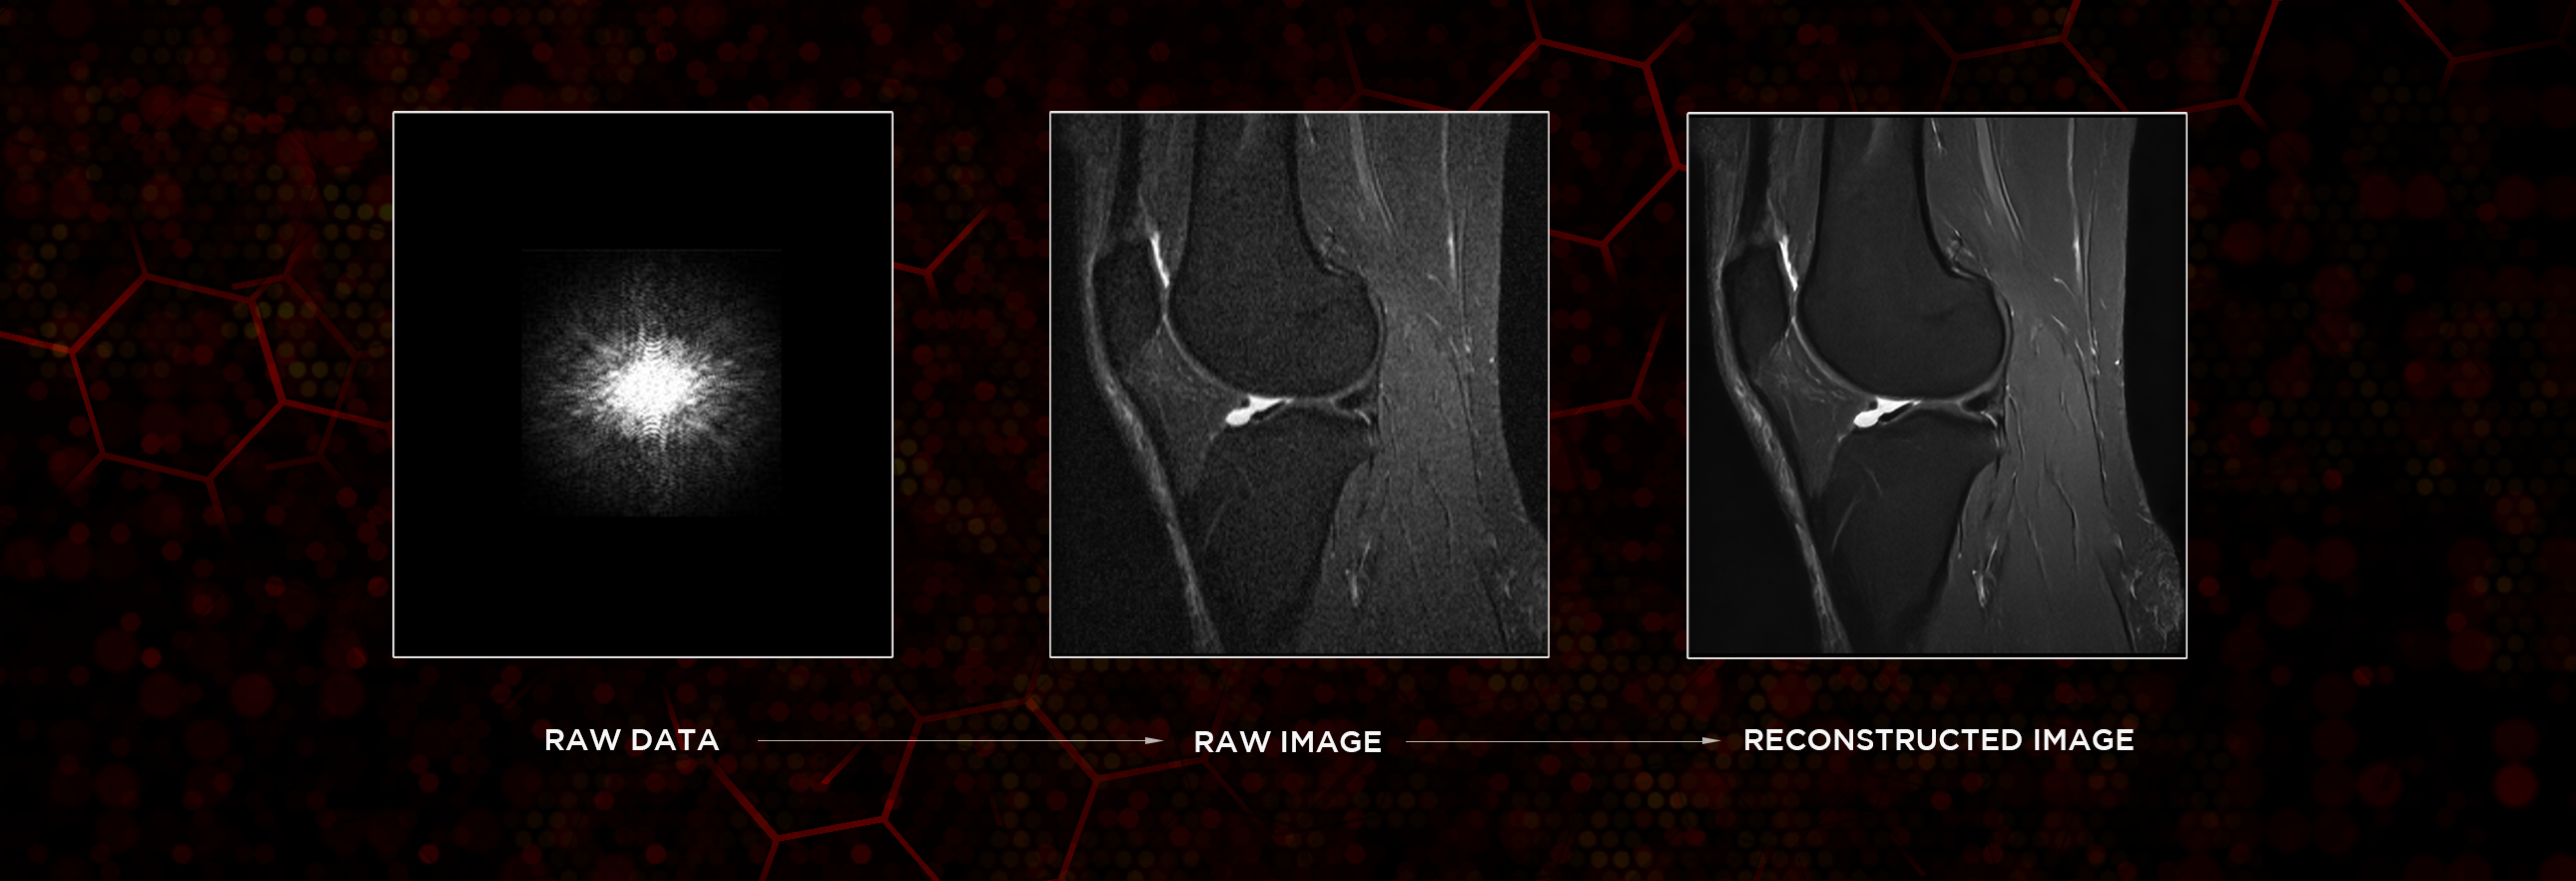

Il sistema e-SPADES esegue l'acquisizione e la ricostruzione dei dati: HyperSpeed* consente di velocizzare l’acquisizione, mentre HyperClarity, applicato all’immagine ricostruita, migliora la risoluzione e la qualità complessiva dell’immagine. In questo modo, la tecnologia e-SPADES con AI perfettamente integrata sul dispositivo, assicura una prestazione efficiente e ad alta velocità.

Entrate nella nuova era dei sistemi Esaote con HyperClarity, basato su SwiftMR™, un marchio registrato di AIRS Medical Inc. Questa funzione avanzata integrata, migliora significativamente la qualità dell’immagine aumentando la risoluzione, riducendo il rumore e fornendo ai medici uno strumento potente per risultati clinici di valore.

Ottenete prestazioni eccezionali dimezzando i tempi con HyperSpeed*, l’algoritmo che aumenta la velocità e riduce i tempi di scansione preservando tutta la completezza di informazioni e dettaglio dell’immagine, per assicurare una qualità costante. Questa nuova soluzione supportata da AI consente un risparmio di tempo fino al 60%, ottimizzando l’efficienza degli esami RM, per una miglior assistenza ai pazienti e una maggior produttività.